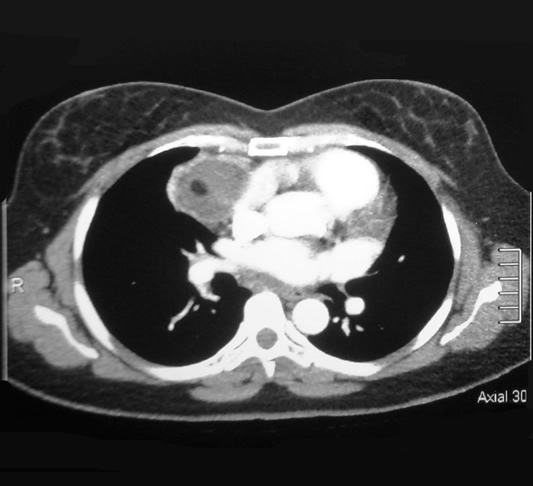

Corte Axial nivel carina bronquial

Corte Mediastinal a la altura de la carina.

Lesión redondeada por delante de aorta ascendente de aspecto homogéneo bien limitada, su cápsula es brillante y bien vascularizada.

Corte Axial nivel hileo pulmonar

Corte Mediastinal a nivel hileo pulmonar.

Lesión redondeada por delante de la aorta y a su derecha la vena pulmonar. contacta con la pared torácica anterior si alterarla.